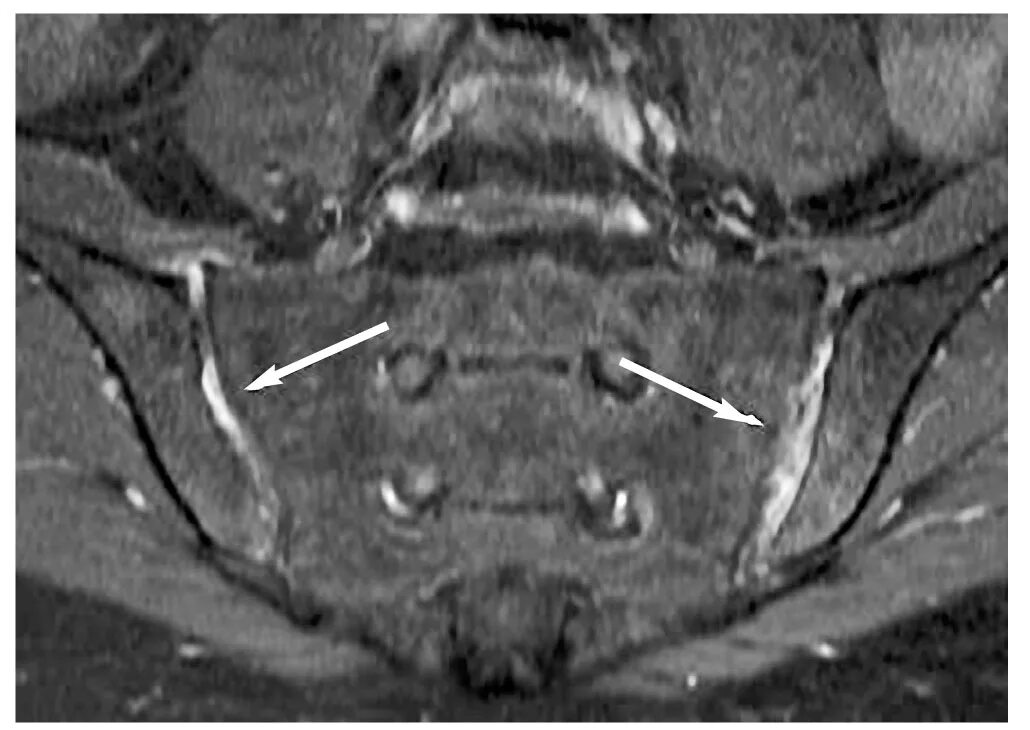

Артрит крестцово подвздошного сочленения